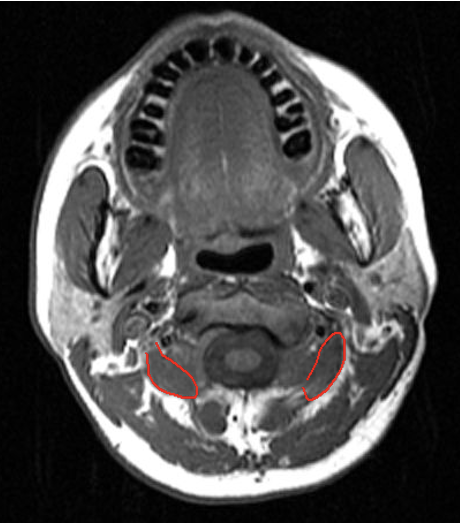

Sub-Occipital

Obliquus Capitis Inferior

-

The C2 vertebral level is identified as a plane 2.5 cm below the mastoid process (3.0 cm below the occipital bone).

Midway between the posterior border of the sternomastoid and the dorsal midline. Depth of 3.0-3.5 cm.